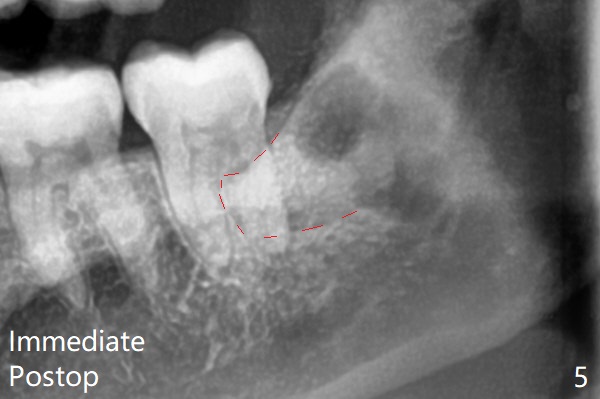

Therefore bone graft seems to be able to be packed mesially (Fig.5: G).  In fact the left Inferior Alveolar Canal is exposed after extraction, collagen plug (P) is placed distal without use of curette around the exposed canal.   Bone graft is highly necessary with patients age>25 with bony defects distobuccal to 2nd molars.